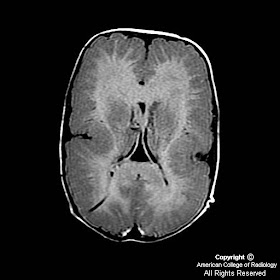

Figure 4, Figure 5, and Figure 6: Multiple axial T2 MR images reveal macrocephaly and polymicrogyria. There are excessive small convolutions of the cortex with an undulating cortical pattern. The white matter signal is increased, consistent with immature myelination. Note the right parietal shunt catheter with normal ventricular size.

Figure 7, Figure 8, and Figure 9 : There is loss of normal gyral architecture, thickened cortex (isointense to gray matter) and indistinct gray-white interface. This pattern is diffuse and is present throughout the brain.

The result of this late neuronal migration disorder is an excessive number of small disorganized cortical convolutions with a thickened cortex. The white matter thickness is usually normal. CT findings consist of excessive small convolutions. These small folds of cortex may resemble pachygyria (incomplete lissencephaly) which results in sparse, broad, flat gyri. In order to best characterize the cortex, MRI is usually performed. Findings on T1 weighted imaging include irregular cortex isointense to gray matter with an indistinct cortical white matter surface. On T2 weighted imaging, two imaging patterns may be present depending on the age of the patient. In infants under 12 months, T2 weighted imaging reveals small, fine undulating cortex with normal 3-4mm thickness. In infants older than 18 months, the cortex is thick and bumpy (6-8 mm) and may contain hypomyelination and cortical infolding. Periventricular calcification may be present if the disorder is caused by TORCH infection, such as CMV.